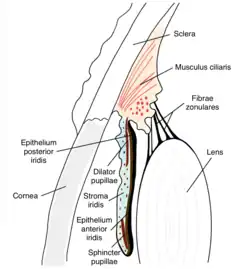

The iris consists of two layers: the front pigmented fibrovascular layer known as a stroma and, behind the stroma, pigmented epithelial cells.

The stroma is connected to a sphincter muscle (sphincter pupillae), which contracts the pupil in a circular motion, and a set of dilator muscles (dilator pupillae), which pull the iris radially to enlarge the pupil, pulling it in folds.

The sphincter pupillae is the opposing muscle of the dilator pupillae. The pupil's diameter, and thus the inner border of the iris, changes size when constricting or dilating. The outer border of the iris does not change size. The constricting muscle is located on the inner border.

The back surface is covered by a heavily pigmented epithelial layer that is two cells thick (the iris pigment epithelium), but the front surface has no epithelium. This anterior surface projects as the dilator muscles. The high pigment content blocks light from passing through the iris to the retina, restricting it to the pupil.[3] The outer edge of the iris, known as the root, is attached to the sclera and the anterior ciliary body. The iris and ciliary body together are known as the anterior uvea. Just in front of the root of the iris is the region referred to as the trabecular meshwork, through which the aqueous humour constantly drains out of the eye, with the result that diseases of the iris often have important effects on intraocular pressure and indirectly on vision. The iris along with the anterior ciliary body provide a secondary pathway for aqueous humour to drain from the eye.

The collarette is the thickest region of the iris, separating the pupillary portion from the ciliary portion. The collarette is a vestige of the coating of the embryonic pupil.[3] It is typically defined as the region where the sphincter muscle and dilator muscle overlap. Radial ridges extend from the periphery to the pupillary zone, to supply the iris with blood vessels. The root of the iris is the thinnest and most peripheral.[4]

From anterior (front) to posterior (back), the layers of the iris are:

- Anterior limiting layer

- Stroma of iris

- Iris sphincter muscle

- Iris dilator muscle (myoepithelium)

- Anterior pigment epithelium

- Posterior pigment epithelium